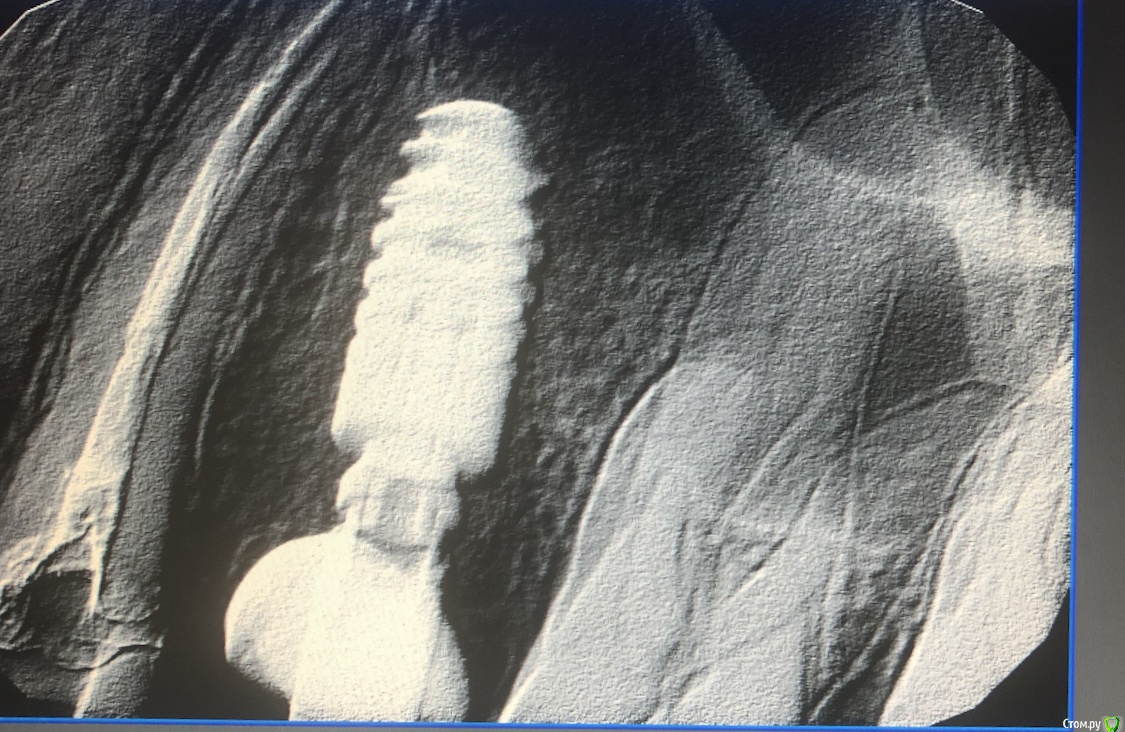

Muhamedgaliev Опубликовано 21 мая, 2019 Поделиться Опубликовано 21 мая, 2019 (изменено) Доброго времени суток уважаемые коллеги. Необходим совет! 16.05.19 провел удаление 2.5, одномоментно установил имплант, немного поднял синус, заложил био-ос. При синусе пробу на разрыв мембраны делал все было гуд. На следующий день пациент жаловался, что отсмаркивание кровяными сгустками, вчера говорит появилось гнойное отделяемое из носа, сегодня отмечает повышение температуры тела до 37,7, ухудшение самочуствия. Подскажите мою тактику действий дальнейших. Изменено 21 мая, 2019 пользователем Muhamedgaliev Ссылка на комментарий

Дмитрий Л. Опубликовано 23 мая, 2019 Поделиться Опубликовано 23 мая, 2019 провел удаление 2.5 По какому поводу было удаление? заложил био-ос Зачем? По рентгену там можно было обойтись только имплантатом. в пазухе образовалось давление из за кровяного сгустка, порвалась мембрана, либо порвалась во время установки импланта. Я думаю что графт травмировал и перфорировал слизистую. диализ 3% перелесью водорода Что ?* наводящем швы Возможно надо будет соустье ушивать вторым этапом. Спасибо вам за кейс. Всё сделали правильно. Sheet happens. Ссылка на комментарий